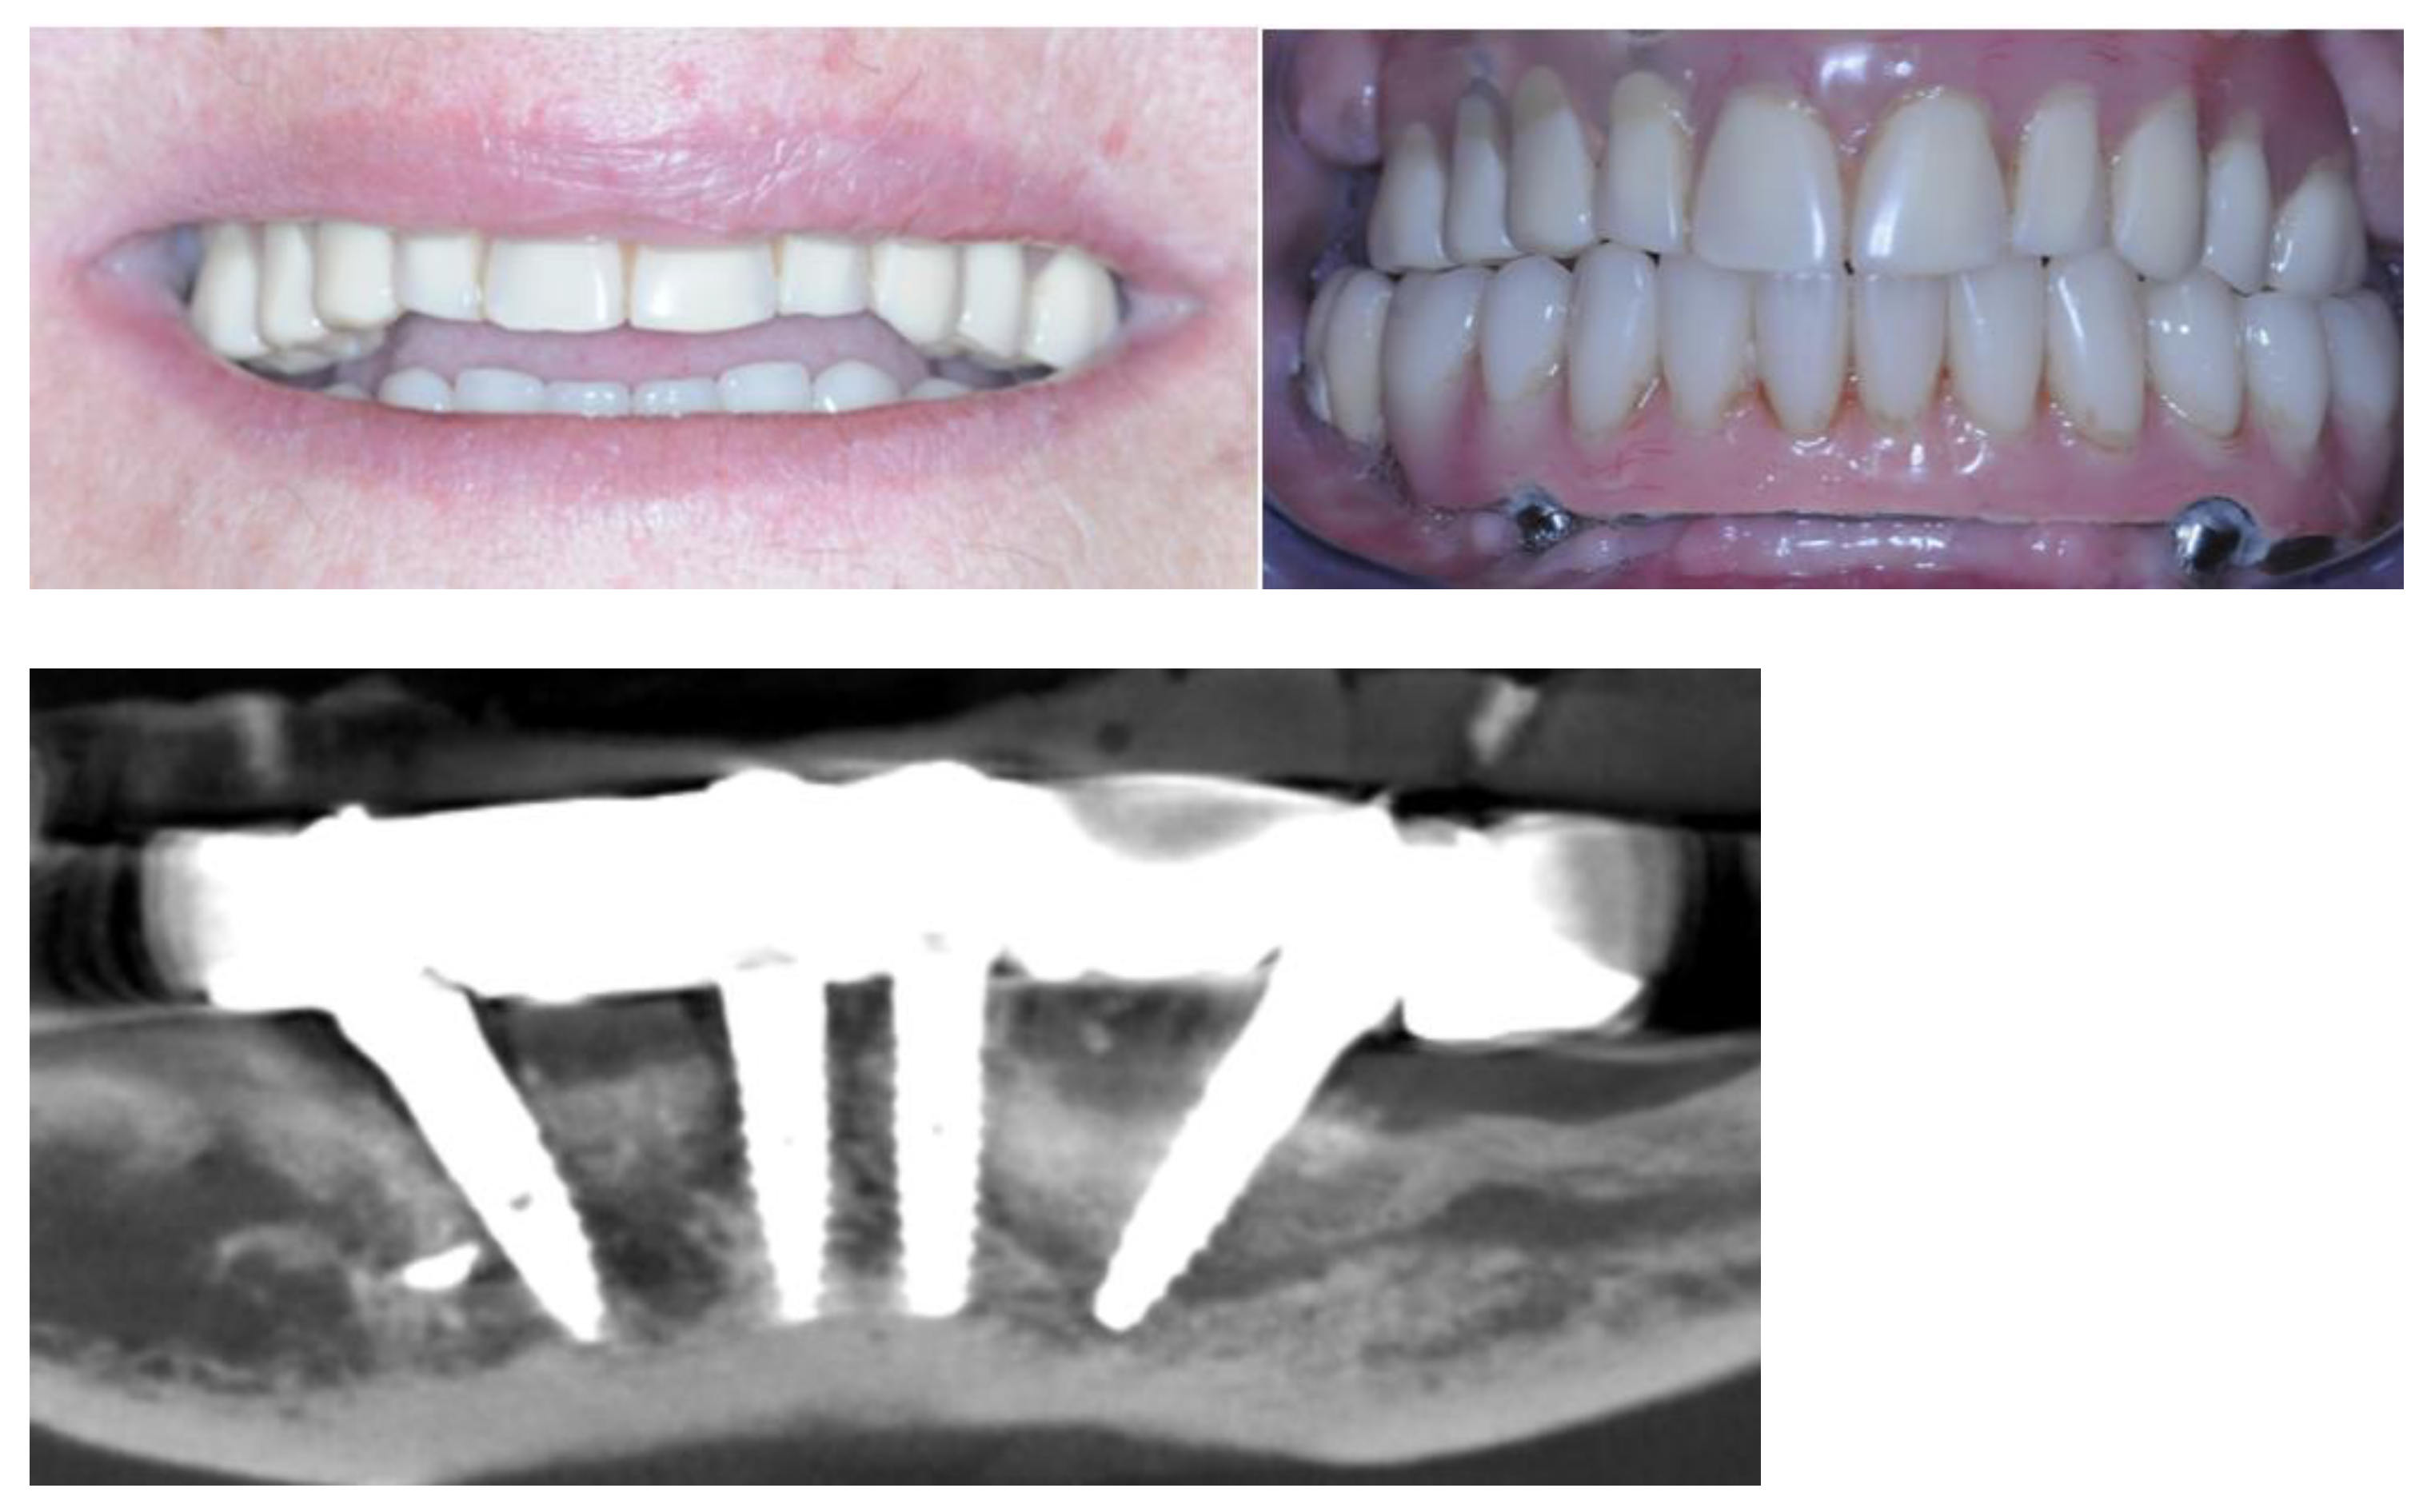

2.5. Definitive Prosthesis